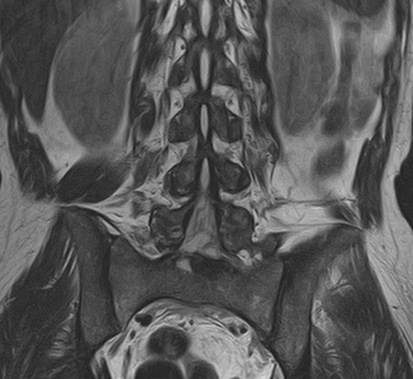

На рисунке – периартикулярная жировая инфильтрация костного мозга: Т1-ВИ; Т2Stir

Жировая дистрофия является результатом эстерификации жира кислотами при воспалении. В целом характерны неспецифические изменения, при АС отражают области внутрикостного воспаления в фазе ремиссии.

МР-картина дегенеративных изменений синовиальной части крестцово-подвздошных суставов, без признаков отека костного мозга